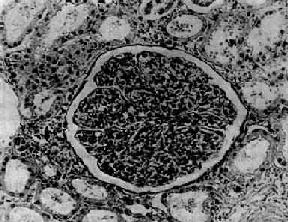

图12-7 弥漫性毛细血管内增生性肾小球肾炎

肾小球内细胞数量增多,系膜细胞和内皮细胞增生并有少量中性白细胞浸润,毛血管腔狭窄

病变为弥漫性,两侧肾同时受累。病变进展较快,主要变化为肾小球内细胞增生。早期,肾小球毛细血管充血,内皮细胞和系膜细胞肿胀增生并有少量中性粒细胞浸润。毛细血管通透性增加,血浆蛋白质可以滤过而进入肾球囊。因此,病人的尿液中常有蛋白、红细胞及白细胞。轻型病人,病变可不再发展,以后逐渐痊愈;比较严重的病例,病变继续发展,肾小球内细胞增生加重。增生的细胞主要为系膜细胞和内皮细胞。增生细胞压迫毛细血管,使毛细血管腔狭窄甚至闭塞,肾小球呈缺血状(图12-7)。此外,肾小球内有多数炎性细胞浸润,主要为中性粒细胞,有时并有少数嗜酸性粒细胞、单核细胞、红细胞、浆液和纤维素性渗出液。镜下,肾小球内细胞数量增多,肾小球体积增大。病变严重时,毛细血管腔内可有血栓形成,毛细血管壁可发生纤维素样坏死。坏死的毛细血管袢破裂出血,大量红细胞进入肾球囊及肾小管腔内,可以引起明显的血尿。不同的病例病变表现形式可能不同。有的以渗出为主,称为急性渗出性肾小球肾炎。有些病变严重,肾小球毛细血管袢坏死,有大量出血者称为出血性肾小球肾炎。